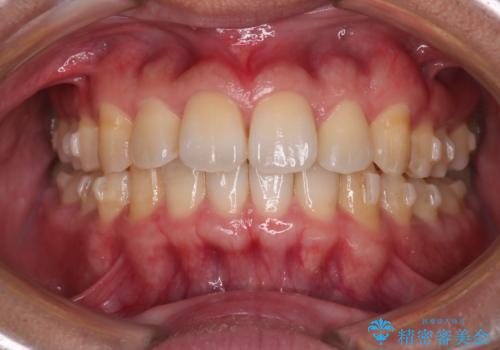

【インビザライン】目立たない矯正で前歯を綺麗に

- 上の歯が出ているのが気になるのを主訴にご来院されました。人前で話すお仕事をされており目立たないマウスピース治療を希望されていました。

口元のEラインは気にならないとのことだったのでインビザラインにて治療していくことにしました。

IPR(歯と歯の間を削る処置)と歯列拡大をすることで前歯を少し下げ、がたつきを改善していく治療計画を立てました。

上の前歯が出ているという主訴が綺麗に改善されました。

その他の部位のがたつき、奥歯の噛み合わせも以前と比べると良くなっています。

目立たない装置で治療期間も10ヶ月と短く終了することができました。